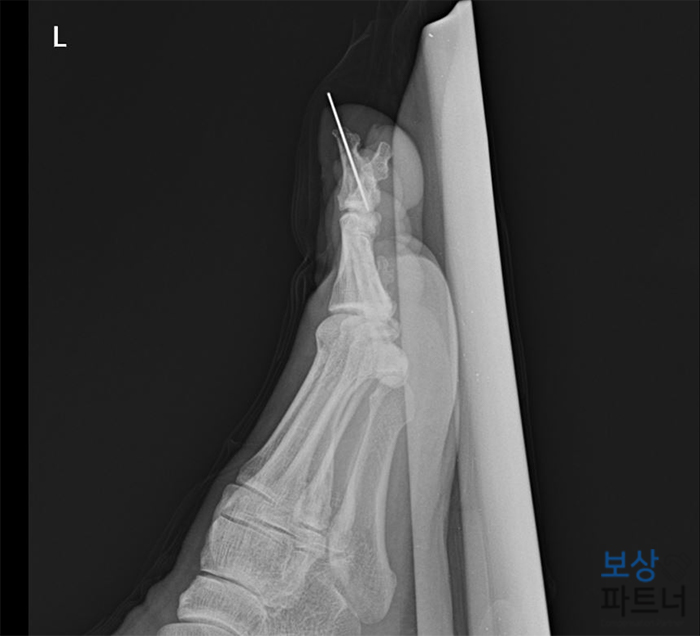

병원 검사 결과, 진단명은 엄지발가락의 골절, 개방성 (S9241) 이었는데요. 개방성 골절이란 뼈가 살 밖으로 노출되는 형태를 말합니다. 우리가 보행하거나 서있을 때 하중을 주로 엄지발가락으로 지지하기 때문에 다른 발가락에 비해 훨씬 중요한 역할을 하는데요.

그렇기 때문에 골절된 부위를 금속 핀으로 단단히 고정시키는 금속 내고정술을 시행하였는데요. 이를 통해 세밀한 골유합이 이루어지고 이후의 관절염 등의 합병증을 방지할 수 있습니다.